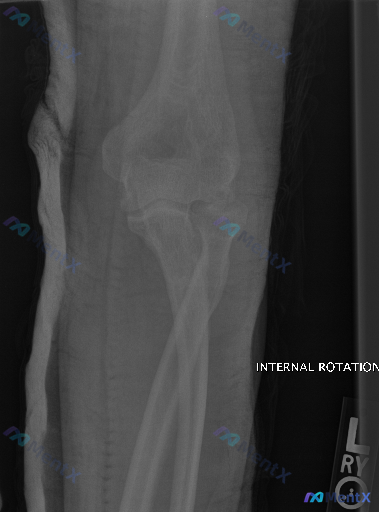

影像背景:左肘关节内旋位X光,患者已行外固定(尺侧可见线性高密度影)。

- 肱骨远端、桡骨近端、尺骨近端骨皮质连续,未见明确骨折线或脱位;

- 关节间隙对位尚可;

- 骨骺未闭,符合青少年发育特征,未见明确Salter-Harris型骨折征象;

- 周围软组织影明显,脂肪垫征因固定显示受限。

核心矛盾:X光报“未见明显骨折脱位”,但临床已经做了外固定。